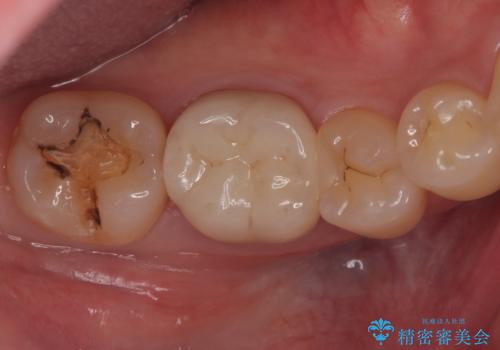

- 主訴:銀色の詰め物が取れてしまった。下の歯は笑うと見えるので、これを機に白くしたい。

保険適用のメタルインレーが脱離しており、歯冠色で審美性、適合性の良いセラミックインレーでのやり替えを提案しました。

メタルインレーが脱離した咬合面の窩洞内は、う蝕を除去し、セラミックインレーの厚みの担保とメタルタトゥー部分の除去を目的に形成を行いました。